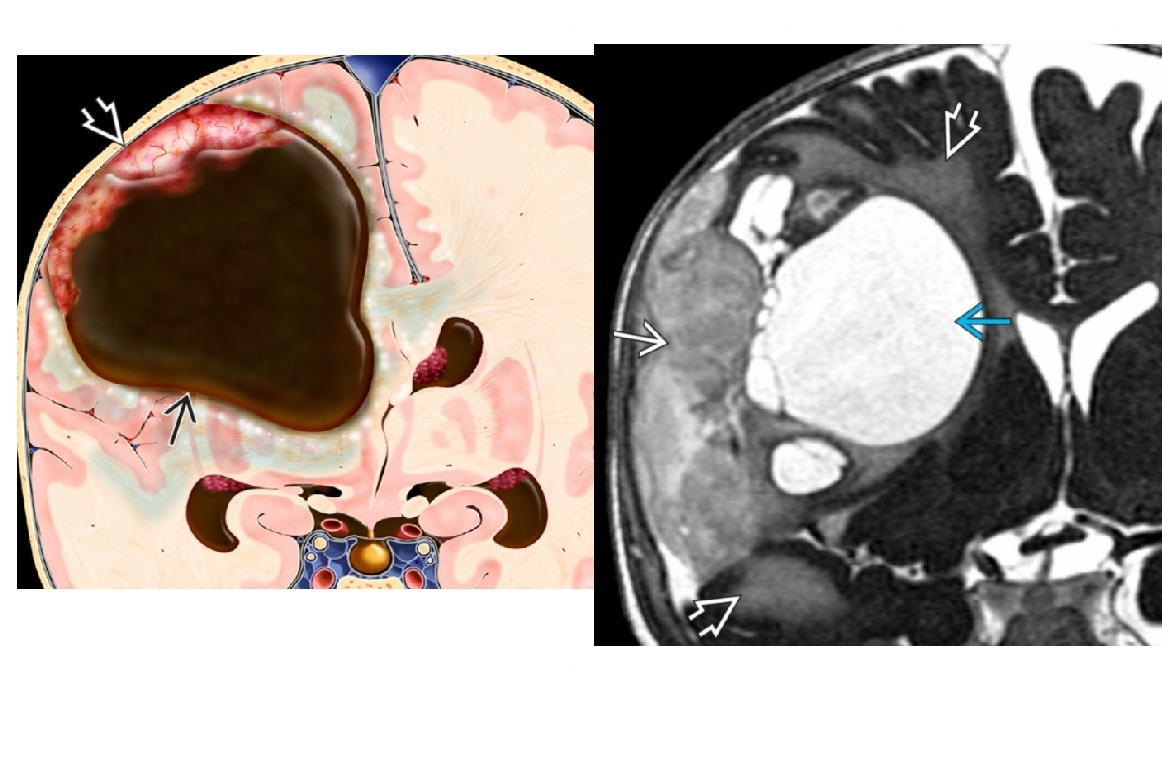

Key difference between Epidural and subdural haematomas?

Epidural - cross midline but not sutures Subdural - DONT cross midline but can cross sutures and dip into the flax cerebri